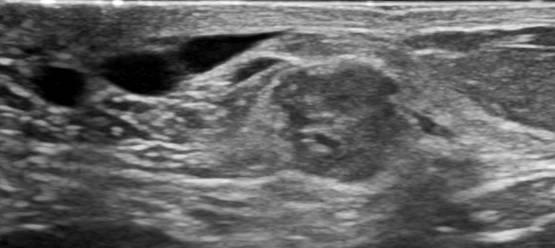

Ung thư vú

Ung thư vú - Ảnh 2

» Thông tin: Nữ giới – 69 tuổi.

» Lâm sàng: Kiểm tra sức khỏe.